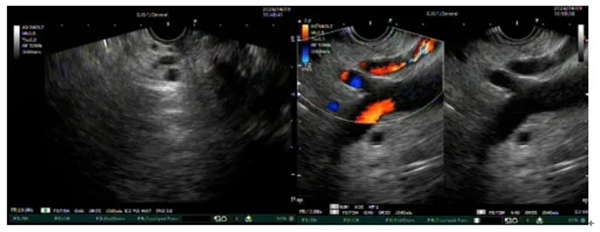

圖示髮(fa)現(xian)消化道早癌并利用(yong)超聲內(nei)鏡判斷(duan)其浸潤深度

微信(xin)截圖_20240417142321.jpg